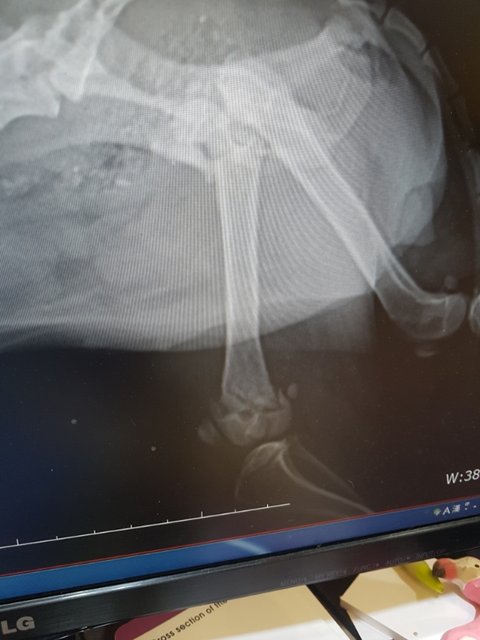

#김제보호소 #교통사고 #뒷다리골반복합골절 #사지말고입양하세요 #유기견입양 #살수있게도와주세요 #치료받을수있게도와주세요

검진을 다녀왔습니다

골반뼈..무릎뼈..복합골절..

다리부분에 피멍이 잔뜩 들어있습니다

여아 1~2살 3.9키로